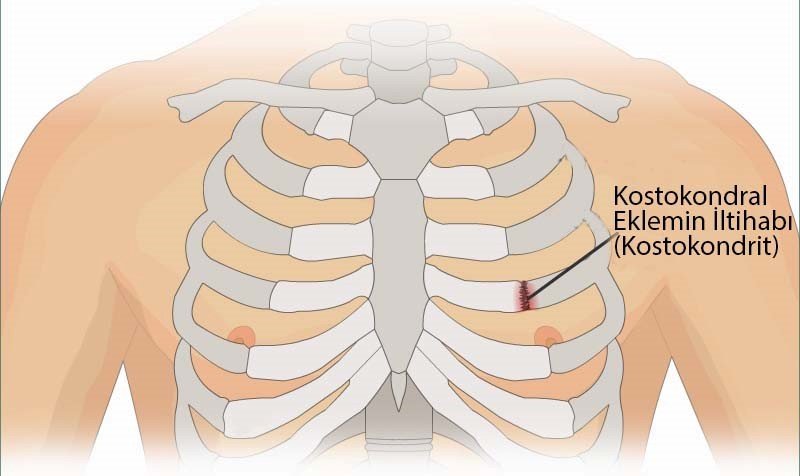

Şəkil

Xəstələr döş sümüyünün yuxarı hissəsində, sternuma yaxın kəskin və ya tədricən artan ağrılardan şikayət edir. Ağrılar adətən birtərəfli olur və hərəkət, öskürək, asqırma, dərin tənəffüs zamanı şiddətlənir. Ağrı zədələnmə tərəfdə qola, çiyinə irradiasiya edir. Ağrılar davamlı olur, remissiya və kəskinləşmə bir-birini əvəz edir. Kəskin dövrdə xəstənin ümumi vəziyyətində dəyişiklik olmur. Xəstənin palpasiyası zamanı ağrı artır. Obyektiv müayinə zamanı zədələnmə zonasında qızartı ilə birgə, 3-4 sm ölçüdə bərk, ağrılı şişkinlik müəyyən olunur.

Döş qəfəsində ağrı verə bilən digər xəstəliklər inkar olunduqdan sonra xəstəliyin diaqnozu qoyulur. Əsas xarakterik əlamətlərdən biri ağrı sahəsində aydın kənarlı, bərk şişkinliyin olmasıdır. Ağrılar bir neçə saat, bəzən bir neçə gün davam edə bilir.

Tietze sindromu ve ya kostoxondrit xondropatiyaların bir forması olub, bir və ya bir neçə yuxarı qabırğa qığırdaqlarının döş sümüyü ilə birləşdikləri yerdə, döş sümüyü-körpücük oynağında aseptik iltihabın yaranması ilə xarakterizə olunur. Adətən proses II –III, az hallarda isə I və IV qabırğalarda baş verir.